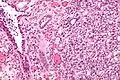

Micrograph of a nephrogenic adenoma. H&E stain. | |

Nephrogenic adenomas are diagnosed under the microscope by pathologists. Microscopically the tumor shows closely packed small tubular structures in edematous stroma. The tubules show considerable variation in size and shape resembling convoluted tubules of the kidney. The single layer of cells lining the tubules are cuboidal with a scant to moderate amount of cytoplasm. In some areas they may have a hobnail appearance. [2]

High mag